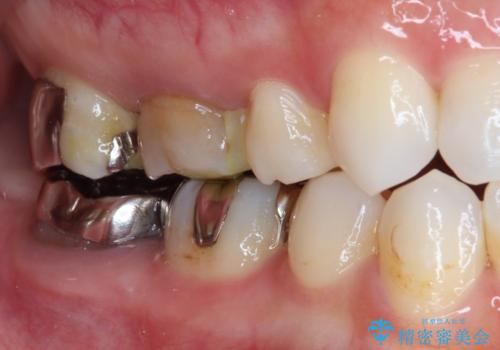

根管治療を施した歯は割れるリスクが上昇するため、詰め物(インレー)ではなく、被せ物(クラウン)にしなければなりません。

適合もよく、機能的に問題もなく、見た目も満足されていました。